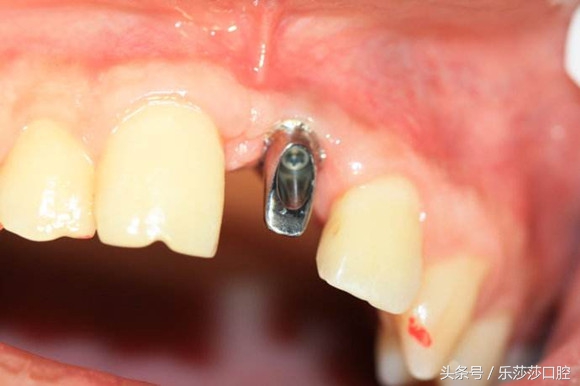

5)连接基台:再切开牙龈,在种植钉上连接一个愈合基台,使软组织在两至三个星期内成形,在这期间病人必须保持口腔卫生,不能出现炎症。

6)修复:当软组织成形后,医生会用永久基台替换愈合基台,开始取模、对修复的牙齿进行设计,然后送到技工室去加工制作。